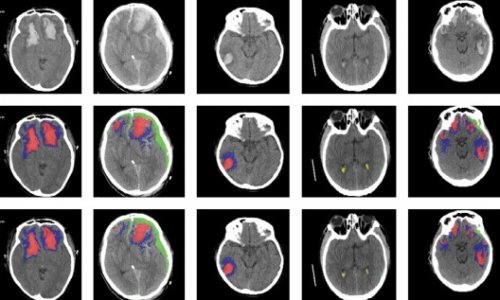

Ai Successfully Identifies Different Types Of Brain Injuries